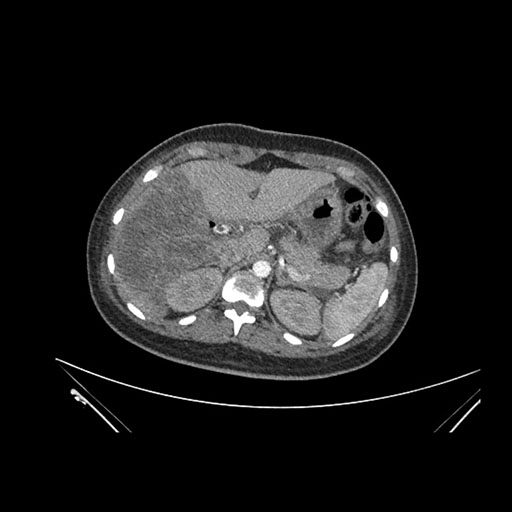

Axial Arterial